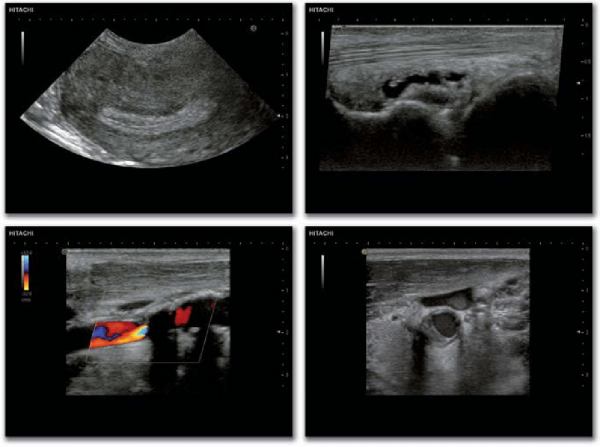

HITACHI HI VISION PREIRUS

Hitachi Hi Vision Preirus je barevný ultrazvukový přístroj střední třídy pro malé ordinace a nemocnice.

Jako ultrazvukový přístroj pro sdílenou službu Preirus uspokojuje potřeby od elastografie, stresového echa a objemového zobrazování.

Prerius je vybaven 19″ LCD monitorem s vysokým rozlišením, který obsahuje dotykovou obrazovku podél spodní části monitoru, která umožňuje efektivnější skenování.